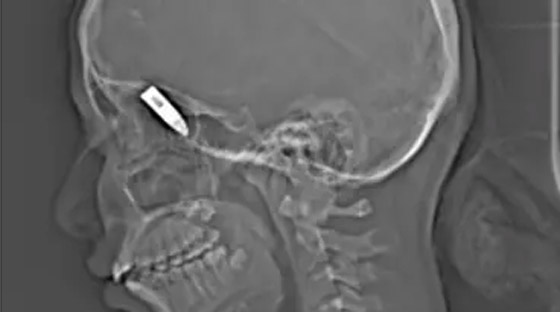

نجح فريق طبي سوداني في عملية جراحية معقدة لأم أصيبت بطلق ناري مباشر، وهي حامل في شهورها الأخيرة. ونقلت وكالة السودان للأنباء اليوم السبت عن سهيل عبدالقادر البشرى مدير الإدارة العامة للطب العلاجي ونائب رئيس لجنة الطوارئ الصحية بوزارة الصحة بولاية الخرطوم أن الفريق الطبي أجرى عملية جراحية لتوليد الأم بسلام ثم استخرج الرصاصة في عملية أخرى، وأن حالة الأم والطفل مستقرة تماماً.

وقال محمد ابراهيم عبدالرحمن المتحدث باسم وزارة الصحة في ولاية الخرطوم ورئيس لجنة الطوارئ الصحية إن العملية أجريت على أيدي متخصصين في أمراضالنساء والتوليد وجراحة المخ والأعصاب وفريق عمل مساند مكتمل ومؤهل.